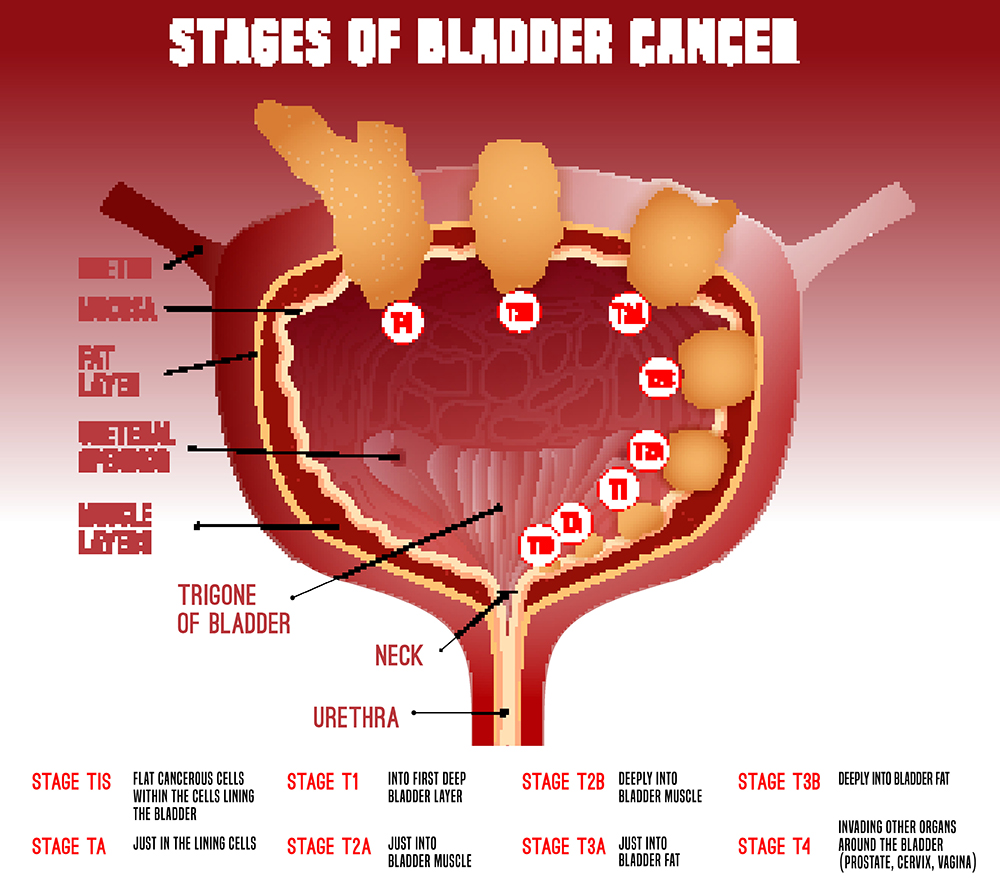

Stages Of Bladder Cancer MEDizzy

https://cdn.medizzy.com/m71nCPyY7NohmQne73hqJ2uhp04=/680x453/img/posts/347500b1-6e6c-48f8-b500-b16e6cb8f820